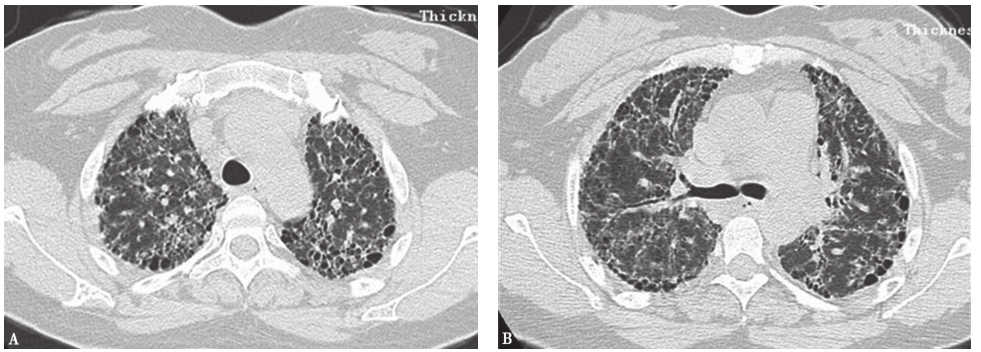

外院胸部CT示两肺散在磨玻璃影、弥漫性小结节影(图1),局部可见牵拉性支气管扩张。

图1外院胸部CT表现

肺部感染性疾病指包括终末气道、肺泡腔及肺间质等在内的肺实质炎症。按病因可分为细菌性肺炎、病毒性肺炎、非典型病原体肺炎(军团菌、肺炎支原体、衣原体感染)、真菌性肺炎、肺结核、其他病原体(立克次体、弓形虫、肺孢子菌、寄生虫等)所致肺炎。临床表现为发热、咳嗽、咳痰,部分可有气促、胸痛、咯血等,体征可有湿啰音,影像学有肺浸润改变。病情严重者有气体交换障碍。肺部感染性疾病可根据症状、体征、影像学表现等做出临床诊断,确诊需依据病原学检查结果。本例患者为中年男性,慢性病程,病程中无发热,主要临床表现为咳嗽、气喘,抗感染治疗效果不佳,结合胸部影像学表现,与普通感染表现不符合。患者平时身体健康,无结构性肺病等慢性病病史,特殊病原体感染可能性亦不大。患者CT特点为两肺磨玻璃影、弥漫性小结节影,须注意与肺结核尤其是血行播散型肺结核鉴别。后者影像学表现为肺野内多发均匀分布的小颗粒状阴影,病变亦可相互融合,呈小斑片状阴影,部分边缘模糊,有的病变呈增殖硬结,部分亦可见纤维化索条状阴影(图2)。本例患者无结核相关发热、消耗等表现,故患肺结核可能性亦不大。

图2血行播散型肺结核胸部CT表现

胸部CT可见两肺弥漫小结节影,大小、分布、密度较均一